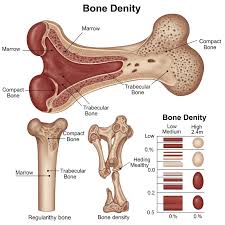

골밀도는 나이가 들수록 자연스럽게 감소하기 때문에 미리 관리하는 것이 매우 중요합니다. 골다공증으로 진행되기 전에

골밀도를 높이는 방법을 제대로 알고 실천하면 뼈 건강을 오래 지킬 수 있습니다.1. 골밀도가 낮아지는 이유 🦴

골밀도는 30세 전후 최고치에 도달한 뒤 꾸준히 감소합니다. 특히 폐경기 이후 여성은 호르몬 변화로 인해 골밀도 감소 속도가 빠릅니다. 칼슘 부족, 운동 부족, 흡연·음주, 햇빛 부족, 만성질환 등이 복합적으로 작용해 뼈가 약해지기 쉽습니다.